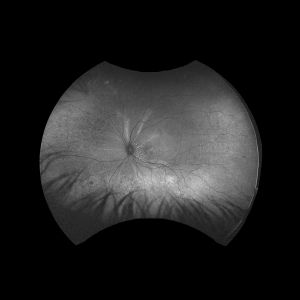

The dominant early sign is multifocal, yellow choroidal swellings on fundus exam. They can resemble multifocal choroiditis or birdshot choroidopathy.[16] Aronow et al. found that of 34 effected eyes, all of them showed yellow-white choroidal infiltrates on ophthalmic examination.[1] Uveal tract thickening can also be seen on fundoscopy, which contributes to the serous retinal detachment often seen.[16] Choroidal folds are common due to the thickened choroid. One hallmark of a choroidal lymphoma is the presence of extra-scleral extension of the choroidal mass, which is often seen with ultrasound imaging. Images 1 and 2 demonstrate choroidal thickening, choroidal folds, and hyper-autofluorescent flecks in the macula in a patient presenting with uveal lymphoma.

Angiography can help to localize the layer that the infiltrates reside and can show hypofluorescent areas due to the blocking effect of sub-RPE masses. If RPE atrophy has occurred, hyperfluorescent areas may be seen.[19] It has been noted that ICG is the preferred form of angiography for uveal lymphoma over fluorescein angiography (FA) as ICG yields more reproducible findings.[1][20]